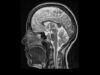

MRI Basics-part2 Mediube Subscribe Subscribed 3 1173 videos 0% 19 Views 0 Likes 2025-01-25 Radiology and Diagnostic StudiesImagingMRIRadiology & Imaging By Mediube 0 Comments (بازدید 19 بار, بازدیدهای امروز 1 ) Show more PREV MRI Basics-part1 Mediube 2025-01-25 NEXT MS white matter lesions First Look MRI Mediube 2025-01-25 You might be interested in 0 Ultrasound Podcast PERICARDIAL TAMPONADE LEARN THIS Mediube 2025-05-12 0 How to read an MRI of the brain Mediube 2025-01-20 0 Clinical Case Pulmonary Abscess Mediube 2025-01-15 0 How Do X-rays Work Mediube 2025-09-06 0 Pneumonia (Right Middle Lobe): Explanation of Chest X-ray Findings Mediube 2024-04-15 0 hand plastering Mediube 2024-01-11 0 Ultrasound Video showing Amoebic liver abscess Mediube 2025-01-29 0 Consolidation Radiology | Lecturio Mediube 2024-04-08 0 Systematic Interpretation of Shoulder MRI How I do it Mediube 2024-12-02 0 How to Read CT Sinus Scans – A Layperson’s Guide Mediube 2024-08-24 Lung Abscess Explanation of Chest X-ray Findings Mediube 2025-01-22 0 Rotator Cuff MRI Everything You Need To Know Mediube 2024-11-26 LEAVE YOUR COMMENT Cancel replyYour email address will not be published. Required fields are marked * Save my name, email, and website in this browser for the next time I comment. Δ